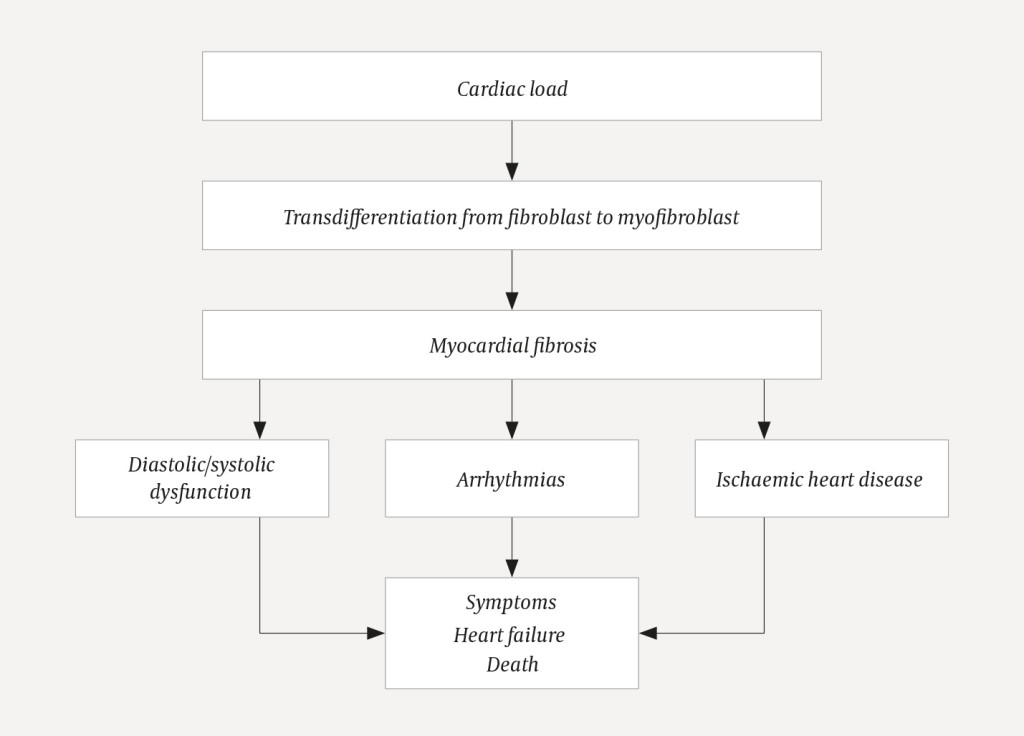

When cardiac damage and stress occur, various substances cause fibroblasts to become activated and transdifferentiate into myofibroblasts (2)−(7) (Figure 2) (8). The myofibroblasts increase the production of proteins that are deposited in the extracellular matrix (2–5). Collagen I, which accounts for about 80 % of the collagen in the myocardium, makes the myocardium stiffer and increases most in myocardial fibrosis (7, 9, 10). Cross-linking makes the collagen matrix stiffer and more difficult to break down with proteinases (2, 3, 5, 11). Fibrosis occurs as a result of net collagen production. Fibrosis restricts the supply of oxygen and nourishment to the myocardium (2, 3). Myocardial fibrosis causes electrical and structural changes that predispose patients to arrhythmias, heart failure and ischaemia (12). Figure 3 summarises the pathophysiology and consequences of myocardial fibrosis.